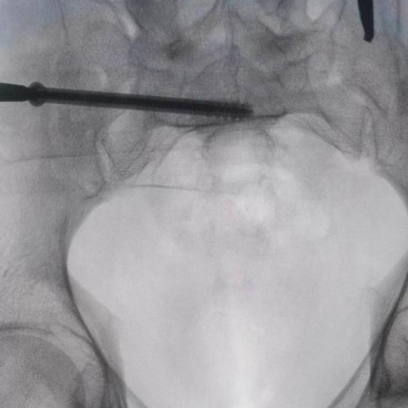

圖為透視下見置入的骶髂螺釘,位置、長(zhǎng)度精準(zhǔn),無絲毫偏差